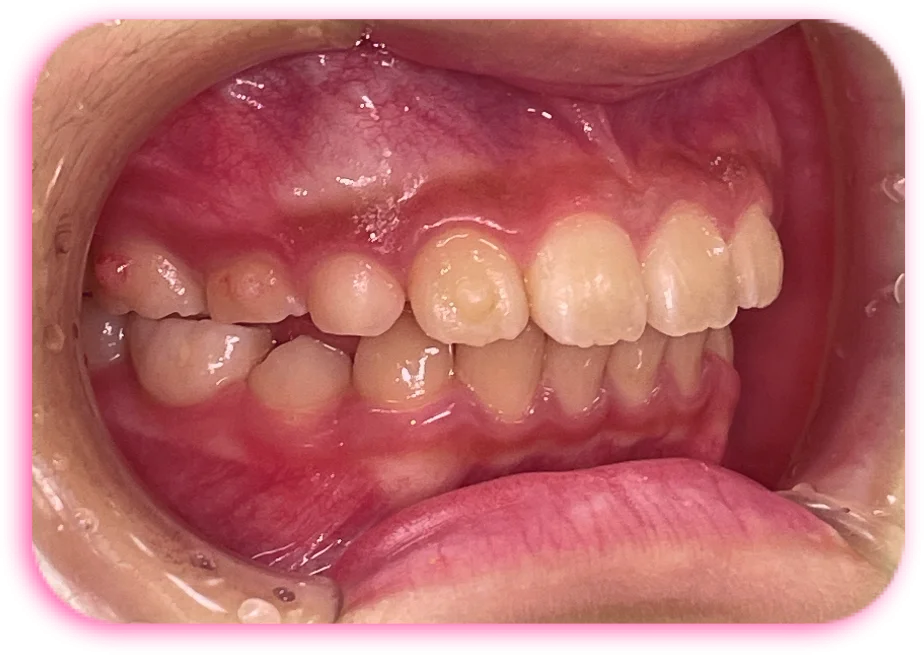

治療前

| 相談内容(主訴) | 出っ歯が気になる |

|---|---|

| 診断結果/行った治療内容 | 上顎前突/インビザライン矯正 |

| 治療期間/回数 | 1.5年/18回 |

| 治療費用 | 80万円 |

| 治療のリスク/副作用 | 歯の移動に伴い歯肉退縮を起こすことがあります/顎関節に症状が出ることがあります |